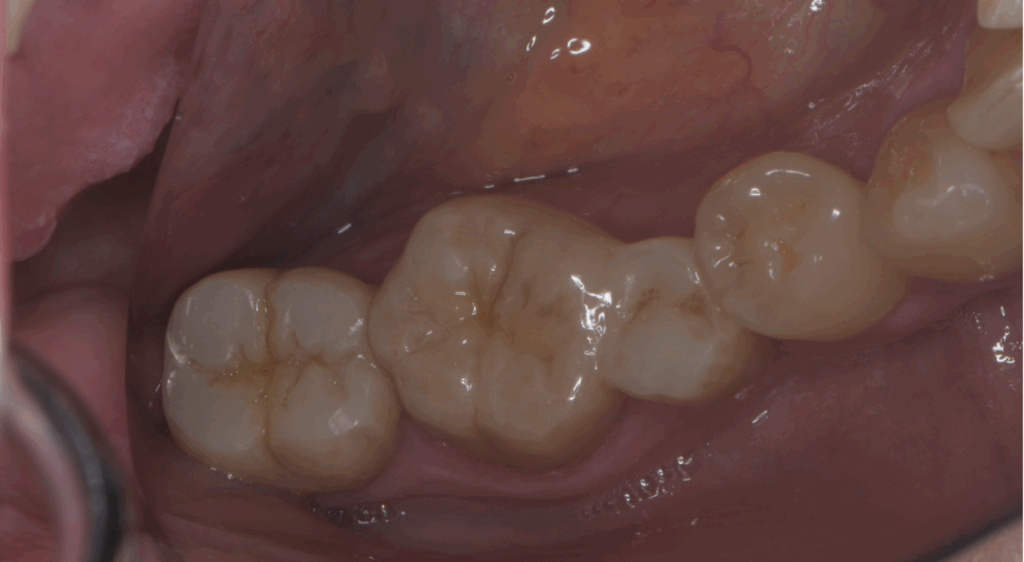

👉 臨床的には、3~6か月で黒い影が縮小し、1年前後で完全に骨が回復するケースも多くあります。

症例1:抜歯宣告からの回復

「他院で『抜歯しかない』と言われましたが、精密根管治療で半年後には骨が戻り、歯を残せました。」